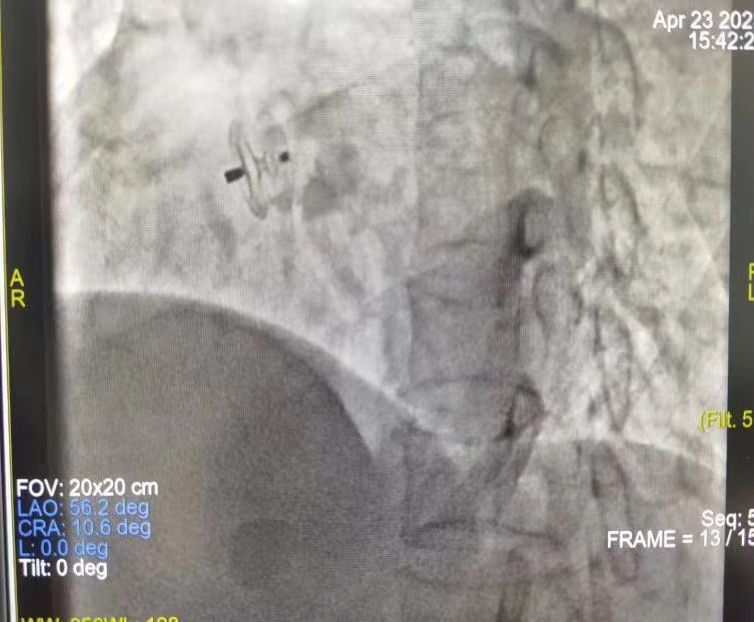

经心内科对其进行PFO封堵术(卵圆孔未闭封顶术)治疗后,患者症状完全缓解出院。

微创介入手术通过在局部麻醉下穿刺大腿的股静脉,将封堵器通过导管推送至心脏并定位于卵圆孔,使其关闭,从而阻止异常血流,术后仅仅遗留一个穿刺点,这种方法安全有效,可以明显改善患者症状,具有避免开胸、创伤小、手术时间短、恢复快等优点。